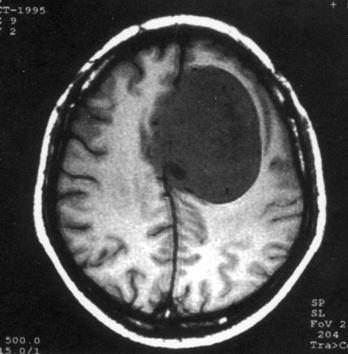

问题 病历摘要:??患者,男,40岁。发作性左下肢抽搐1年余,每次发作3~5分,每周发作1~2次。每次发作后感左下肢乏力,约半日后可自行恢复。既往身体健康。体检:神清,头顶部偏右有局限性骨性隆起(1.5×1.5cm),左鼻唇沟稍浅,伸舌居中。感觉、运动无明显异常。左浅反射减退,左下肢腱反射稍亢进,左Babinski征(-)。 术前的检查和治疗应包括下列哪些?提示:初步诊断考虑脑膜瘤,拟手术治疗。